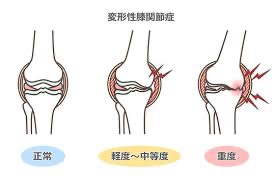

加齢による関節の変化(変形性膝関節症)

膝のクッションの役割をしている軟骨がすり減って、痛みや動きにくさが出やすくなってくる状態です。

イメージで言うと「車のタイヤがすり減って、ガタガタしている状態」に近いです。

クッションがなくなることで、スムーズに動けなくなってしまいます。

長年頑張って動いていると、こうなってしまうのも無理もないことです。